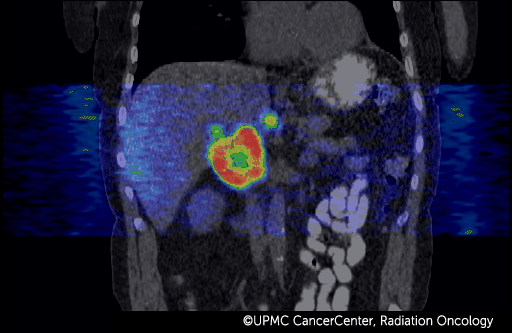

4D PET-CT combines positron emission tomography (PET) with computed tomography (CT) to take advantage of these faster, more accurate technologies.

- Captures the movement of your organs and tumor over time, while also recording the metabolism of the tumor.

- Creates the most complete and accurate imaging data on your tumor and critical organs.

- Makes it possible to see the makeup and function of your tumor.

By understanding the functional and material aspects of the tumor, your radiation oncologist can conclude which parts of the tumor need more (or less) radiation for more effective treatment.

4D PET and 4D CT images fuse together and show:

- How your tumor moves.

- How your breathing affects the tumor.

- How movement of nearby organs affects the tumor.